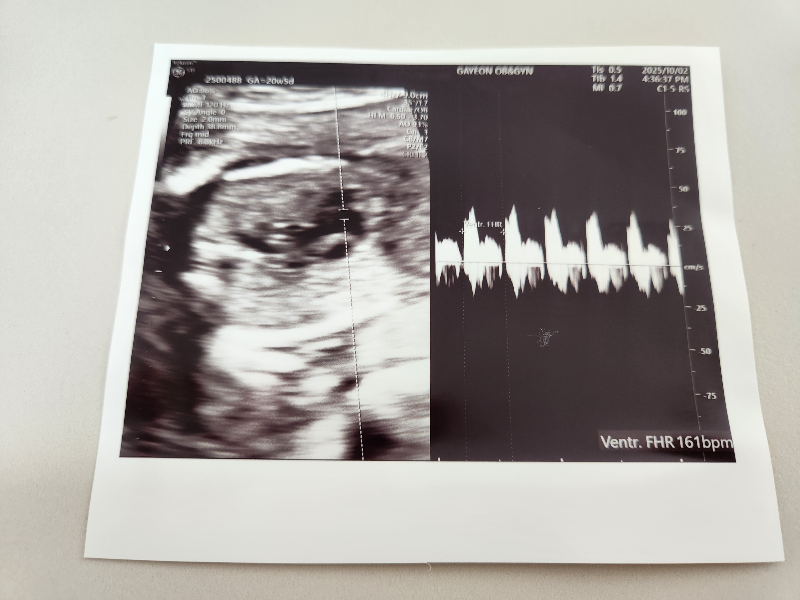

태아의 심장소리도 확인합니다

심장이 아주 잘 뛰어주고 있습니다.